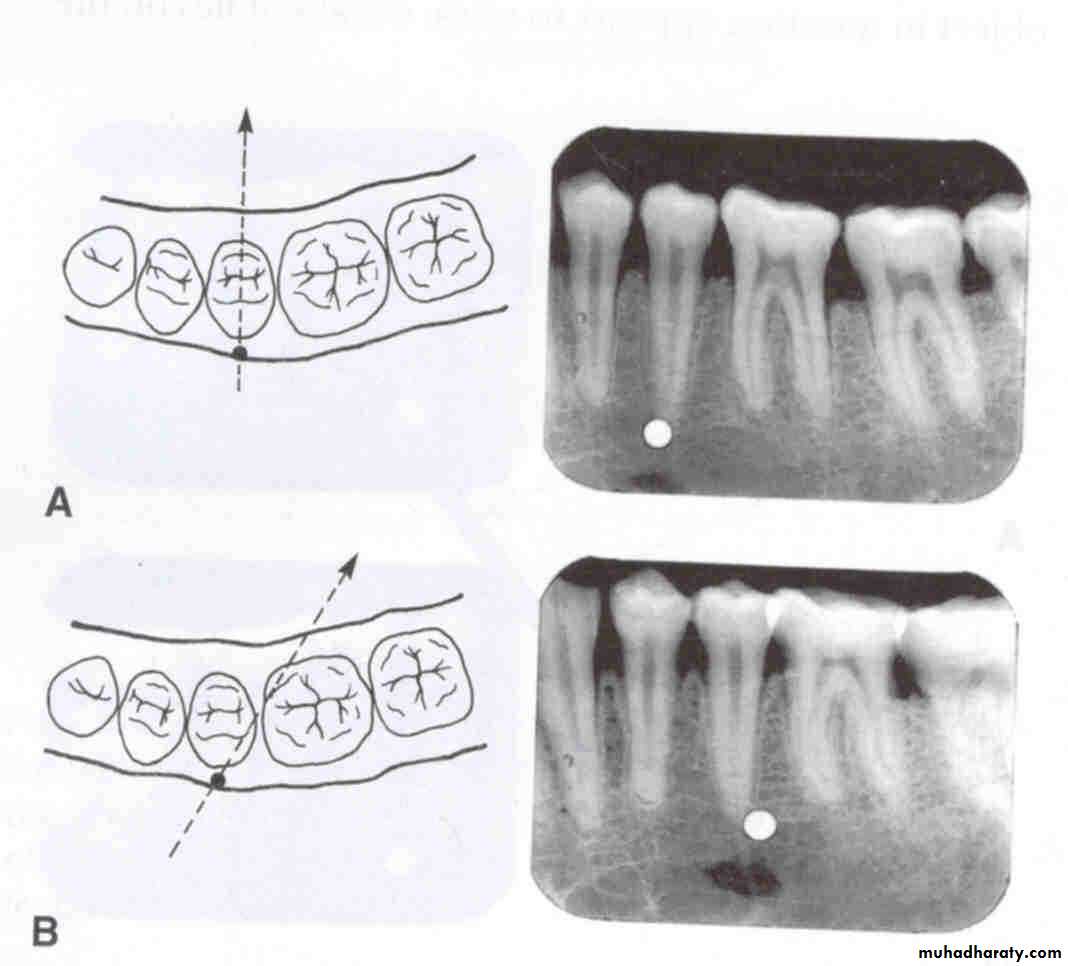

Vertical movement of the tube head and x-ray beam

In moving from the maxillary periapical to the bitewing and from the bitewing to the mandibular periapical, the tube head moves down and the beam is redirected upward (opposite direction; decreased vertical angulation).

Vertical movement

In the diagram at left, the tube head is moved upward and the beam is directed downward. On the radiograph, the buccal object of interest (yellow) moves down (opposite to tube head movement) in relation to the second premolar and the lingual object of interest (red) moves up (same direction as tube head) in relation to the second premolar.

In the diagram at left, the tube head is moved downward and the beam is directed upward. On the radiograph, the buccal object of interest (yellow) moves up (opposite to tube head movement) in relation to the second premolar and the lingual object of interest (red) moves down (same direction as tube head) in relation to the second premolar.